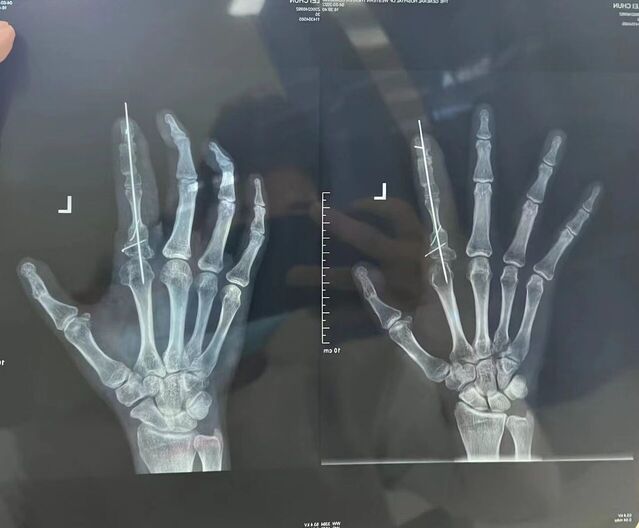

昨天的手术。

微信图片_20231008195909.jpg 微信图片_20231008195912.jpg 微信图片_20231008195906.jpg 微信图片_20231008195903.jpg 微信图片_20231008195829.jpg 微信图片_20231008195839.jpg 微信图片_20231008195836.jpg 微信图片_20231008195945.jpg 微信图片_20231008195939.jpg